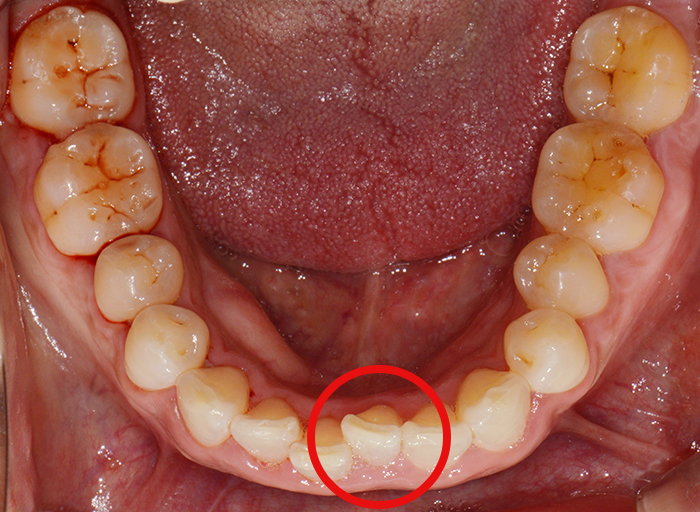

전체적인 치열을 확인하기 위해서는 정면에서 찍은것보다 아래와 같이 입을 벌린 상태에서 찍은 모습을 보면 보다 자세히 알 수 있습니다.

앞에서 말씀드린 것처럼 빨간색으로 표시한 부분의 한쪽이 안쪽으로 삐뚤게 꺾여있네요. 그리고 주변 치아들도 몇개도 고르지 않고 올 바른 치열을 방해하고 있는 것이 보이시죠?